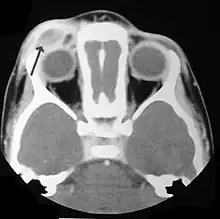

Imaging may be evident in chest X-rays with micronodular and reticular changes of the lungs with cyst formation in advanced cases. MRI and High-resolution CT may show small, cavitated nodules with thin-walled cysts. MRI scan of the brain can show three groups of lesions such as tumourous/granulomatous lesions, nontumourous/granulomatous lesions, and atrophy. Tumourous lesions are usually found in the hypothalamic-pituitary axis with space-occupying lesions with or without calcifications. In non-tumourous lesions, there is a symmetrical hyperintense T2 signal with hypointense or hyperintense T1 signal extending from grey matter into the white matter. In the basal ganglia, MRI shows a hyperintense T1 signal in the globus pallidus.[36]